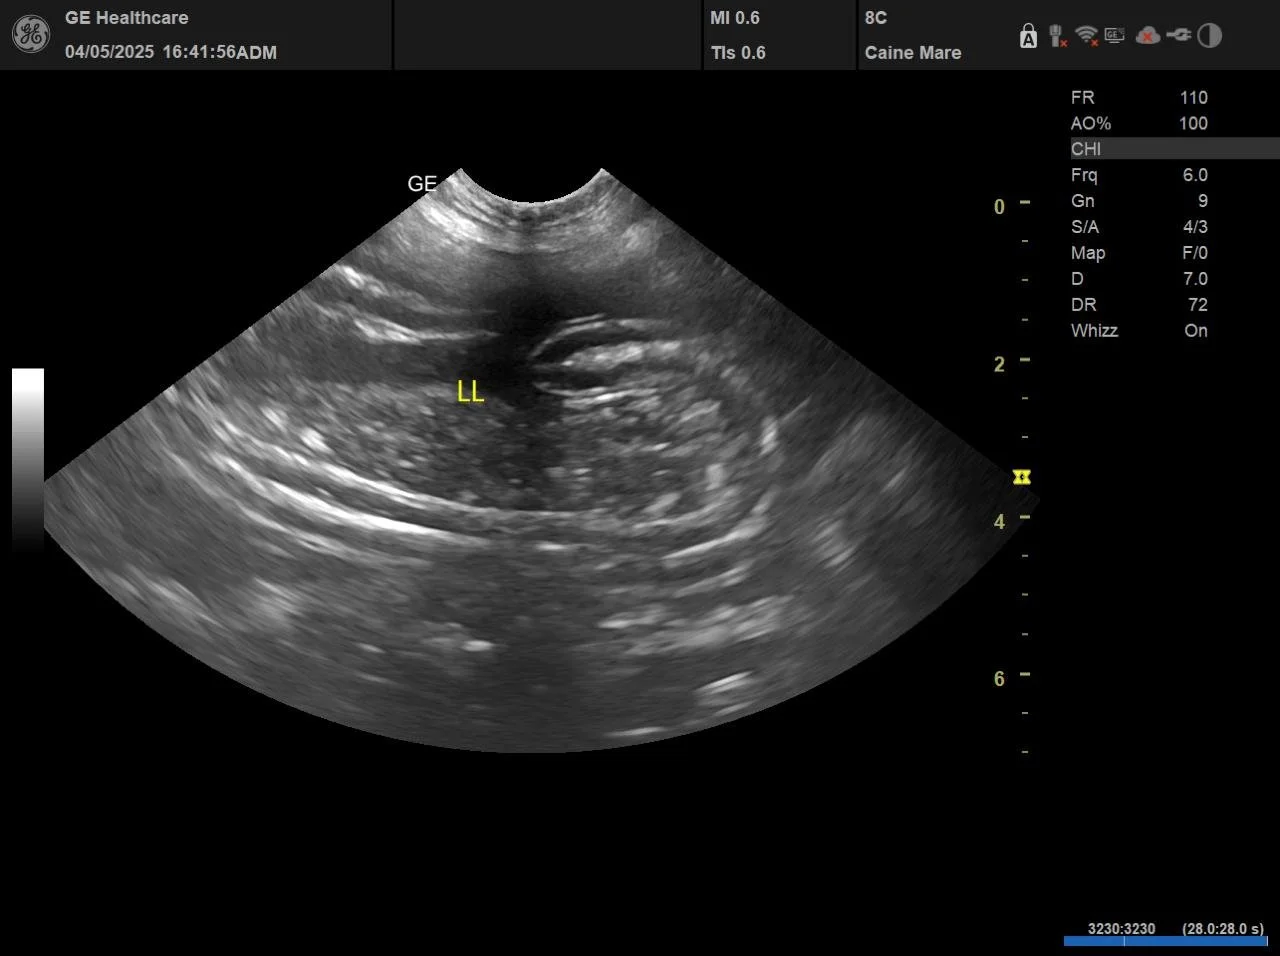

Simptomele de tip vărsături sau vărsături asociate cu diaree pot masca afecțiuni abdominale grave. În cadrul examinării inițiale, s-a efectuat ecografie abdominală POCUS, ca parte standard a protocolului de triere în cazul manifestărilor digestive.

Examinarea ecografică a indicat:

• steatită în cadranul cranial, predominant în zona duodenului proximal;

• o lamă fină de lichid peritoneal, puncționabilă.